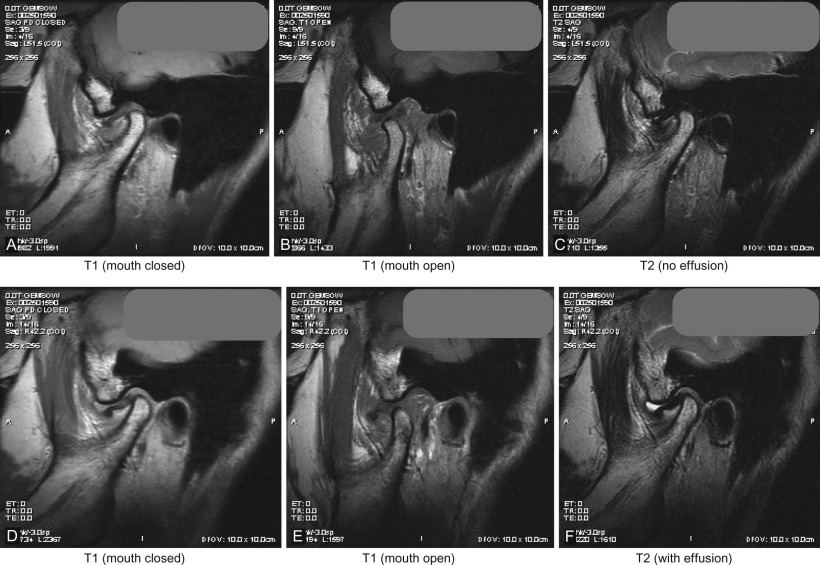

Computed tomography (CT ) permits detailed assessment of the TMJ, allowing views in the axial, coronal, and sagittal planes and also makes 3D volumetric reconstruction possible. CT is particularly useful in the assessment of bony structures and pathologies such as TMJ ankylosis. Indeed a “bony window” setting helps accentuate this effect, while a “soft-tissue” setting helps visualize nonosseous structures more clearly. However, despite the latter, the TMJ disk and other soft tissue structures in the region of interest are often impossible to view with CT alone. Higher radiation exposure and cost can be brought down considerably with the use of cone beam computed tomography (CBCT) technology but image artefacts from metallic objects, whether dental restorations or metallic prostheses near or in the field of interest, produce a starburst pattern of scatter. This may mask the detail required for TMJ assessment and other image modalities may be sought. Magnetic resonance imaging (MRI) is widely accepted as the study of choice to visualize the TMJ disk and ligaments, adjacent soft tissues, inflammatory changes, and the presence of joint effusion. Depending on image weighting, two commonly used studies are T1 images, which are fat-enhancing and provide excellent anatomic detail such as disk position/displacement, and T2 imaging, which is used in identifying inflammatory processes and/or the presence of joint effusion in the TMJ. Open and closed views (see Fig. 3.10.3 ) are captured to understand changes in joint biomechanics and disk pathology. As with CT imaging, artefacts can occur with metallic objects such as dental restorations. Aneurysmal brain clips or patients with indwelling cardiac pacemakers are contraindications for MRI study. Volumetric 3D reconstruction is also not easily achievable unlike with CT imaging, however Costa et al. conducted a study to define the diagnostic value of a method for 3D reconstruction of MRI images for the assessment of TMJ and found the method to be a useful and an accurate tool for this purpose, particularly when focusing on internal derangement.